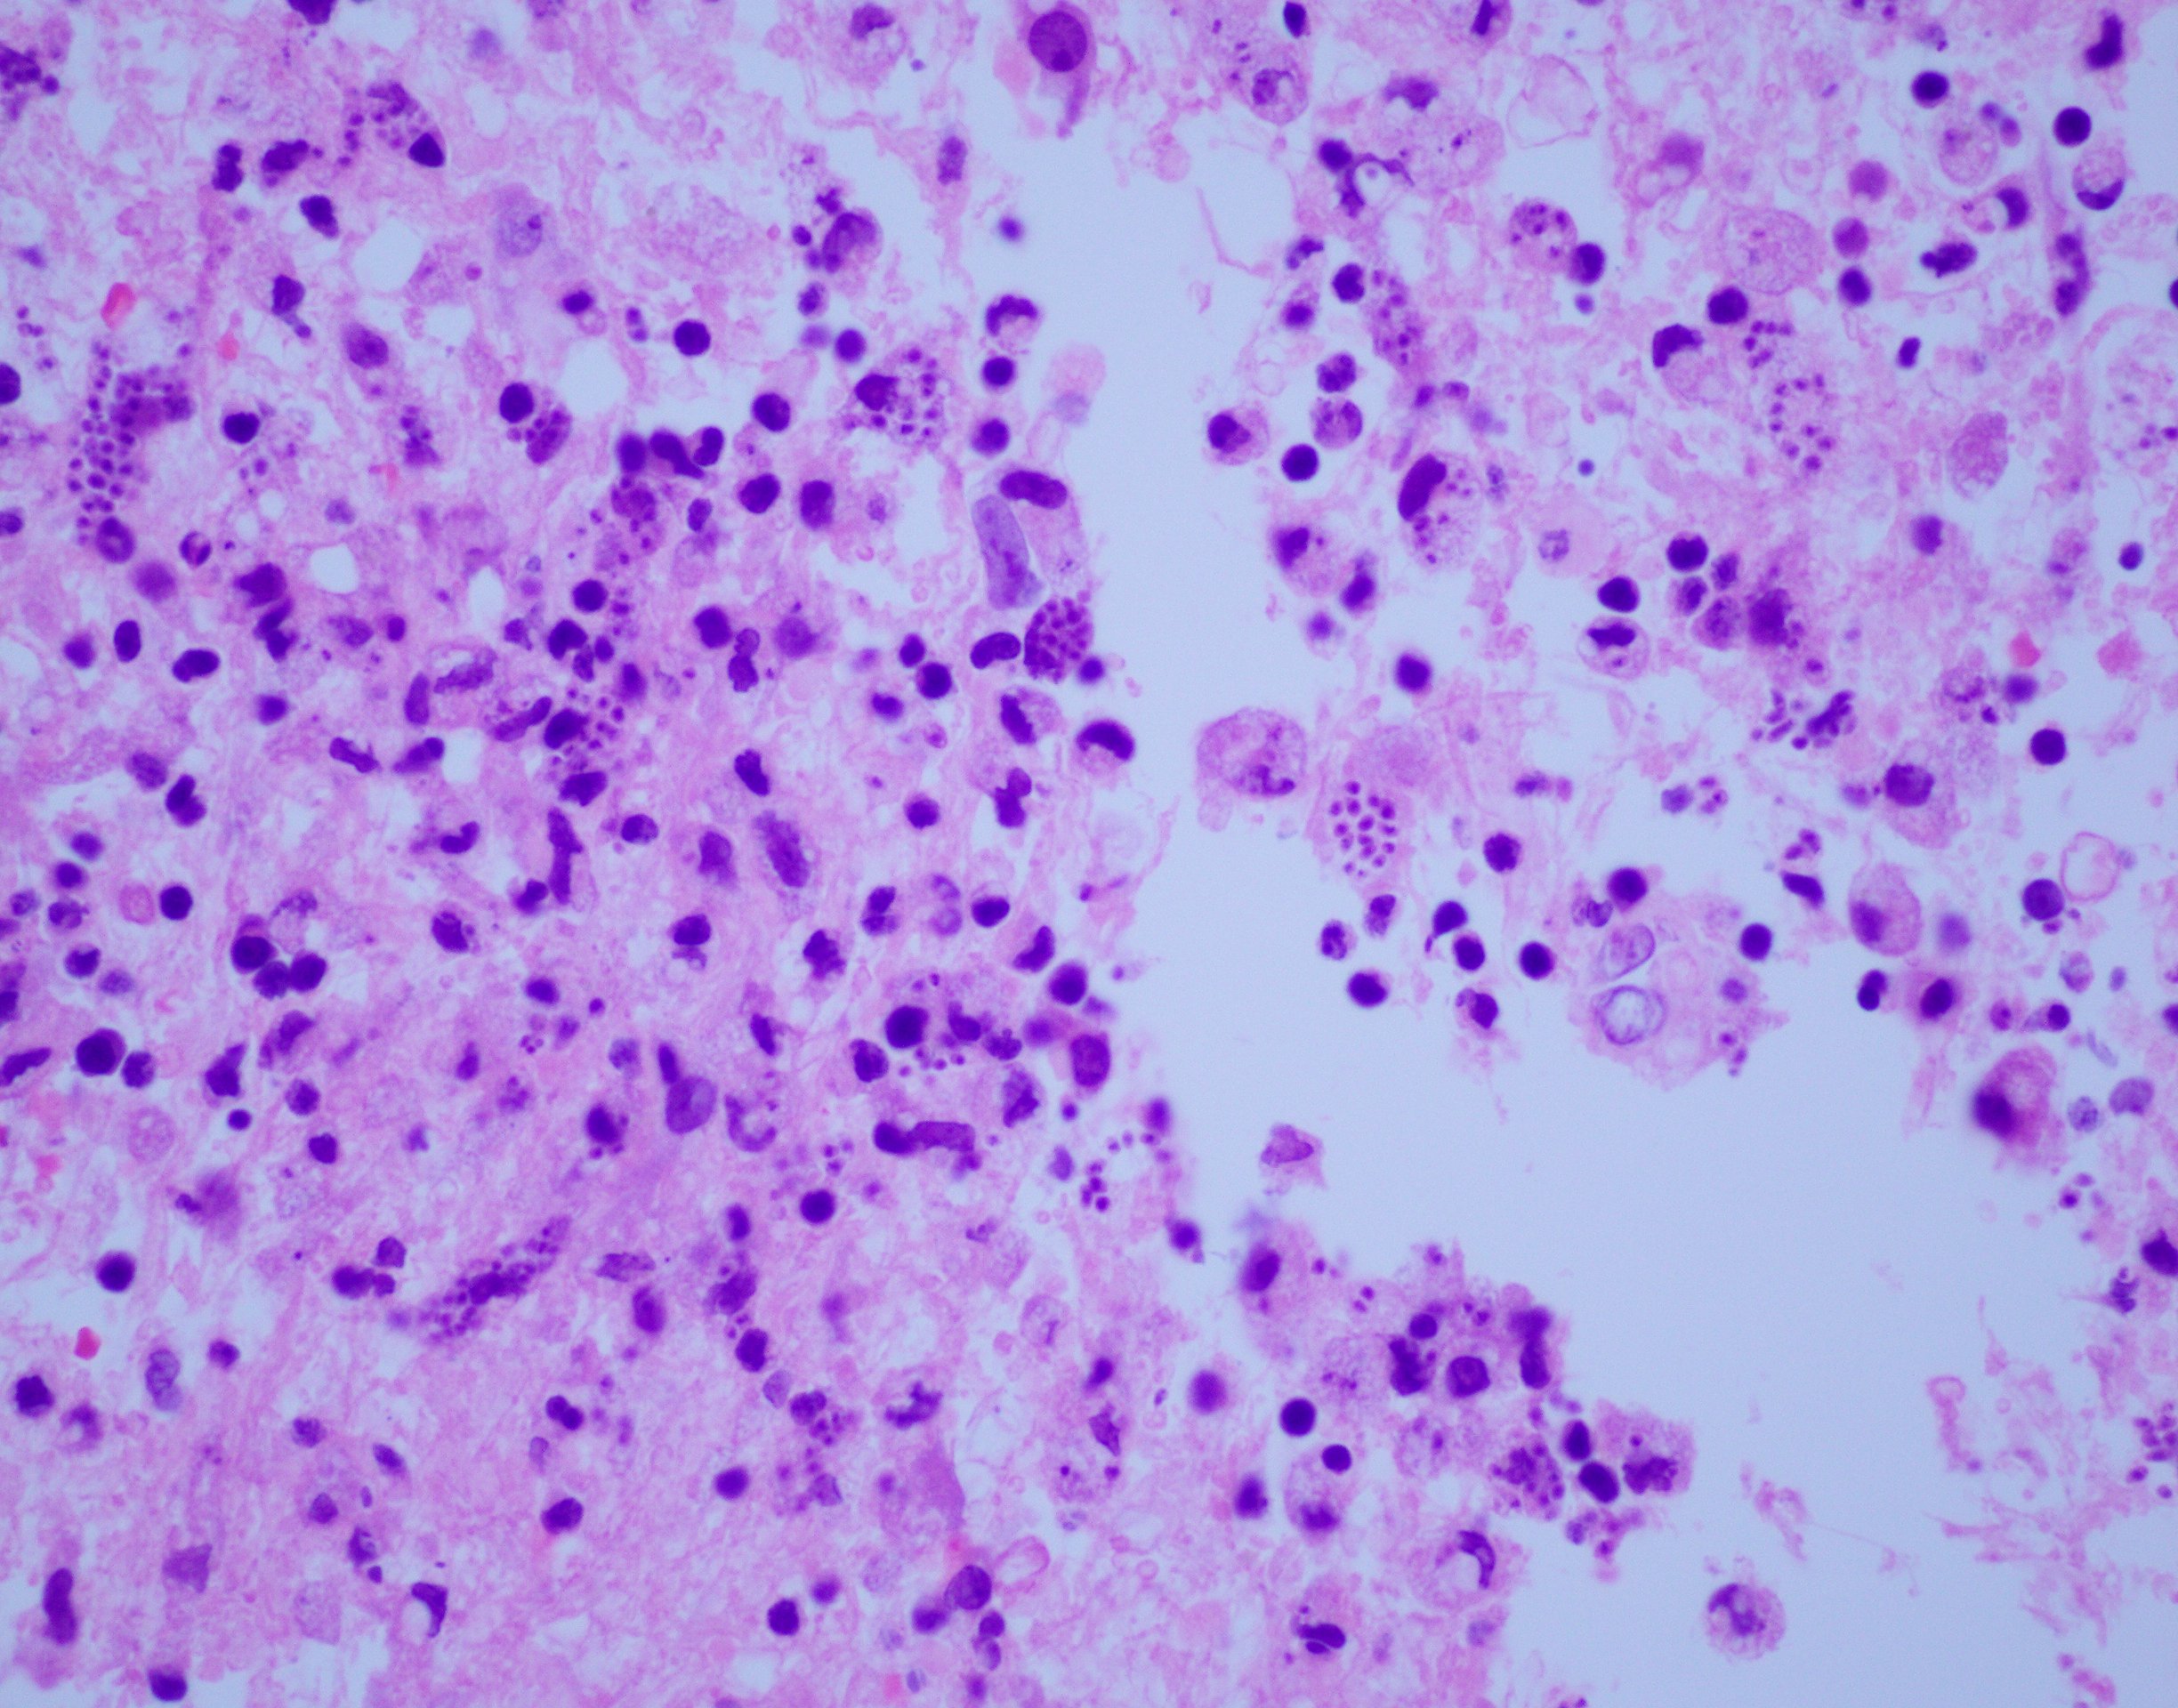

Case Presentation: An 88-year-old female from Peru with history of hypothyroidism, rheumatoid arthritis treated with oral methotrexate, and multiple recent transient ischemic attacks presented with altered mental status, difficulty speaking, and right sided weakness. The patient was unable to fully participate in any examination or conversation. Initial labs, including HIV tests, were unremarkable and head MRI demonstrated bilateral white matter lesions with thick, peripheral enhancing located within the frontoparietal regions causing extensive edematous changes. At this point, the differential included bacterial or fungal infections, primary CNS lymphoma, metastatic disease, multiple sclerosis, posterior reversible encephalopathy syndrome, or acute disseminated encephalomyelitis. A lumbar puncture found elevated lymphocytes, no oligoclonal bands, and negative bacterial and viral serology; brain biopsy demonstrated intracellular parasites which prompted PCR of the sample for Trypanosoma cruzi (T. cruzi.) After confirmation with the CDC, the patient received two weeks of benznidazole therapy before dying of respiratory failure.

Discussion: Diffuse, enhancing lesions on MRI with edematous changes requires a broad differential with a plan to differentiate between malignancy and infections. Specifically, primary CNS lymphoma and bacterial abscesses should be considered. In the absence of obvious infectious signs, brain biopsy may be required. Despite their infrequency, intracellular parasitic infections must be considered once other, more common, diagnoses are ruled out. Chagas disease is due to a secondary reactivation of T. cruzi and is most frequently seen in individuals from Latin America. While commonly causing cardiac and intestinal complications, T. cruzi has also been known to cause cerebral illness, most notably in immunosuppressed patients. Diagnosis of cerebral Chagas necessitates ruling out more common pathologies and a high clinical suspicion.